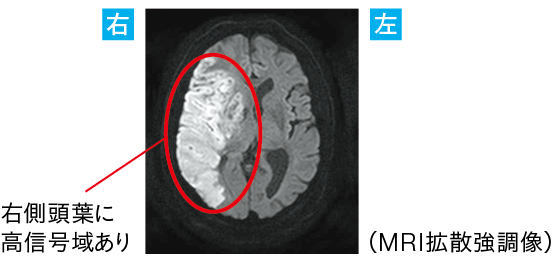

●MRI拡散強調画像から、右中大脳動脈の閉塞により脳幹が脳浮腫に圧迫され、上行性網様体賦活系(覚醒機能の維持)が障害されたと考えられる

●ただし、意識障害(意識混濁)は「脳」以外にもさまざまな要因で生じる。「意識障害」=「脳」と短絡的に捉えないよう気をつけたい